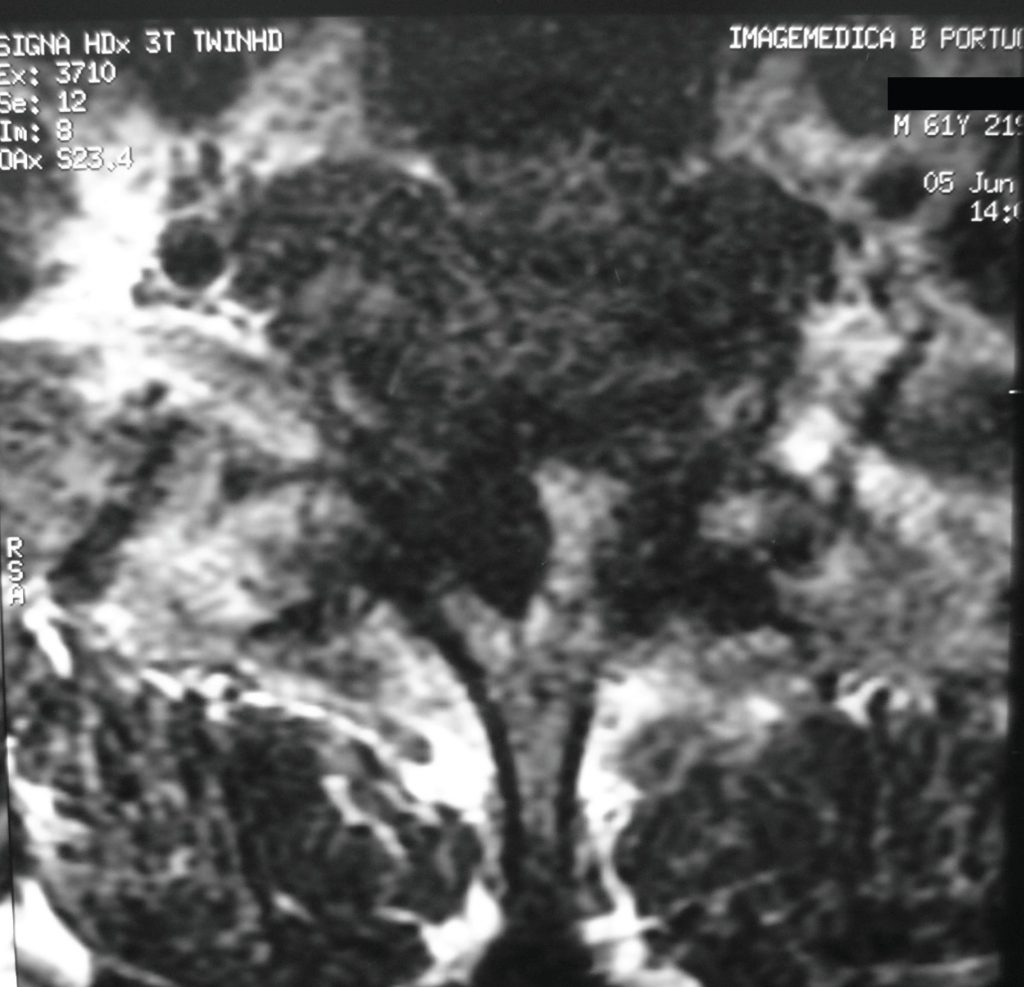

Figure 1B

Axial MRI presented significant compression of bilateral spine